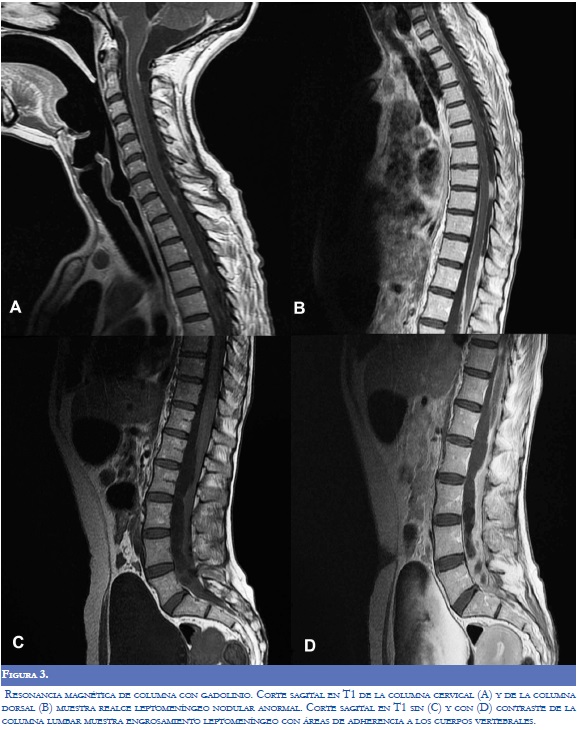

Los laboratorios realizados (hemograma, electrólitos, proteína C-reactiva, VDRL y VIH) fueron normales. Se realizó punción lumbar pero no se obtuvo retorno de líquido cefalorraquídeo (LCR) por bloqueo del espacio subaracnoideo. El LCR se obtuvo por medio de ventriculostomía externa y su análisis mostró hipoproteinorraquia; posteriormente se realizó derivación ventriculoperitoneal y se realizó un segundo análisis de LCR (Tabla 1). La reacción en cadena de polimerasa para tuberculosis fue negativa en LCR (otros análisis se encontraron normales). Los niveles de inmunoglobulina G en sangre fueron positivos para cisticerco (Índice IgG de 4,57; V.R. menor de 0,35). La primera resonancia magnética del cerebro realizada al ingreso al servicio de urgencias mostró marcada hidrocefalia (Figura 1). Después de la ventriculostomía externa, y la colocación de la derivación ventrículoperitoneal, la tomografía axial computarizada del cerebro (TAC) mostró múltiples nódulos calcificados sugestivos de NCC sin edema perilesional (Figura 2). La RM de la médula espinal reveló paquimeningitis generalizada, realce meníngeo y lesiones nodulares sugestivas de NC subaracnoidea (Figura 3). Otros estudios imaginológicos como TAC toracoabdominal con contraste y gamagrafía ósea se encontraron dentro de los límites normales. La biopsia meníngea realizada reveló la presencia de células fibrosas monomórficas rodeadas por tejido colagenosos, sin parásitos, compatible con inflamación crónica o hidrocefalia crónica.

El estadio final se desarrolla cuando los quistes evolucionan a la fase calcificada, donde se convierten en nódulos calcificados e inertes. Esta fase es la más frecuente y el diagnóstico se realiza principalmente mediante la TAC simple, que muestra múltiples lesiones pequeñas hiperdensas sin edema perilesional. Aunque en la RM estas lesiones inactivas pueden realzar con gadolinio, en esta etapa la TAC adquiere más importancia que la RM debido a su sensibilidad para identificar calcificaciones (Figuras 2 y 3).

Otras localizaciones de la NCC incluyen el espacio intraventricular en el 33% de los casos, el cuarto ventrículo es el más afectado, seguido por los ventrículos laterales, tercer ventrículo y por último el acueducto (7). La cisticercosis ventricular se observa en la TAC como lesiones hipodensas que distorsionan el sistema ventricular causando hidrocefalia obstructiva o asimétrica (10). La forma subaracnoidea corresponde al 2-12% de los casos y las imágenes muestran un compromiso difuso con aracnoiditis, hidrocefalia, vasculitis con o sin compromiso isquémico (1). La cisticercosis medular puede ocurrir con menor frecuencia y puede estar asociada con mielopatía debido a la invasión intramedular del quiste (2); los hallazgos radiológicos se resumen en la tabla 2.

El compromiso neurológico se produce por las formas activas e inactivas de la NCC. Las manifestaciones clínicas y los hallazgos imagenológicos dependen de la localización de las lesiones en el SNC, la respuesta inflamatoria, el compromiso en la circulación del LCR y la etapa de la enfermedad. Este caso tuvo una gran variedad de manifestaciones neurológicas estrechamente relacionadas con el compromiso difuso del SNC. En la evaluación clínica y neuroimagenológica se demostró una NCC nodular calcificada con hidrocefalia, compromiso medular y trastornos motores. La TAC y la RMN mostraron una forma meníngea crónica de la NC con compromiso espinal caracterizado por la presencia de hipertensión intracraneal secundaria a aracnoiditis generalizada y adherencias que ocasionaron obstrucción del flujo del LCR e hidrocefalia. Hubo aracnoiditis cerebral y espinal. La paciente tuvo convulsiones recurrentes y síntomas motores explicados por nódulos focales e hidrocefalia, hipertensión intracraneal y aracnoiditis medular, respectivamente.